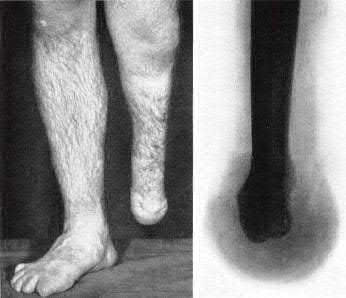

Question 19

A 28-year-old male sustains a closed comminuted tibial shaft fracture.

Two hours post-injury, he develops severe leg pain unyielding to narcotics. His blood pressure is 120/80 mmHg. Intracompartmental pressure monitoring is performed. Based on current guidelines, which measurement dictates an emergent 4-compartment fasciotomy?

Explanation

Acute compartment syndrome is classically defined by tissue hypoperfusion. The absolute compartment pressure is less reliable than the differential pressure (Delta P). A Delta P (Diastolic Blood Pressure minus Compartment Pressure) of less than 30 mmHg is an absolute indication for emergency fasciotomy, as capillary perfusion gradient is lost when tissue pressure approaches the diastolic pressure.